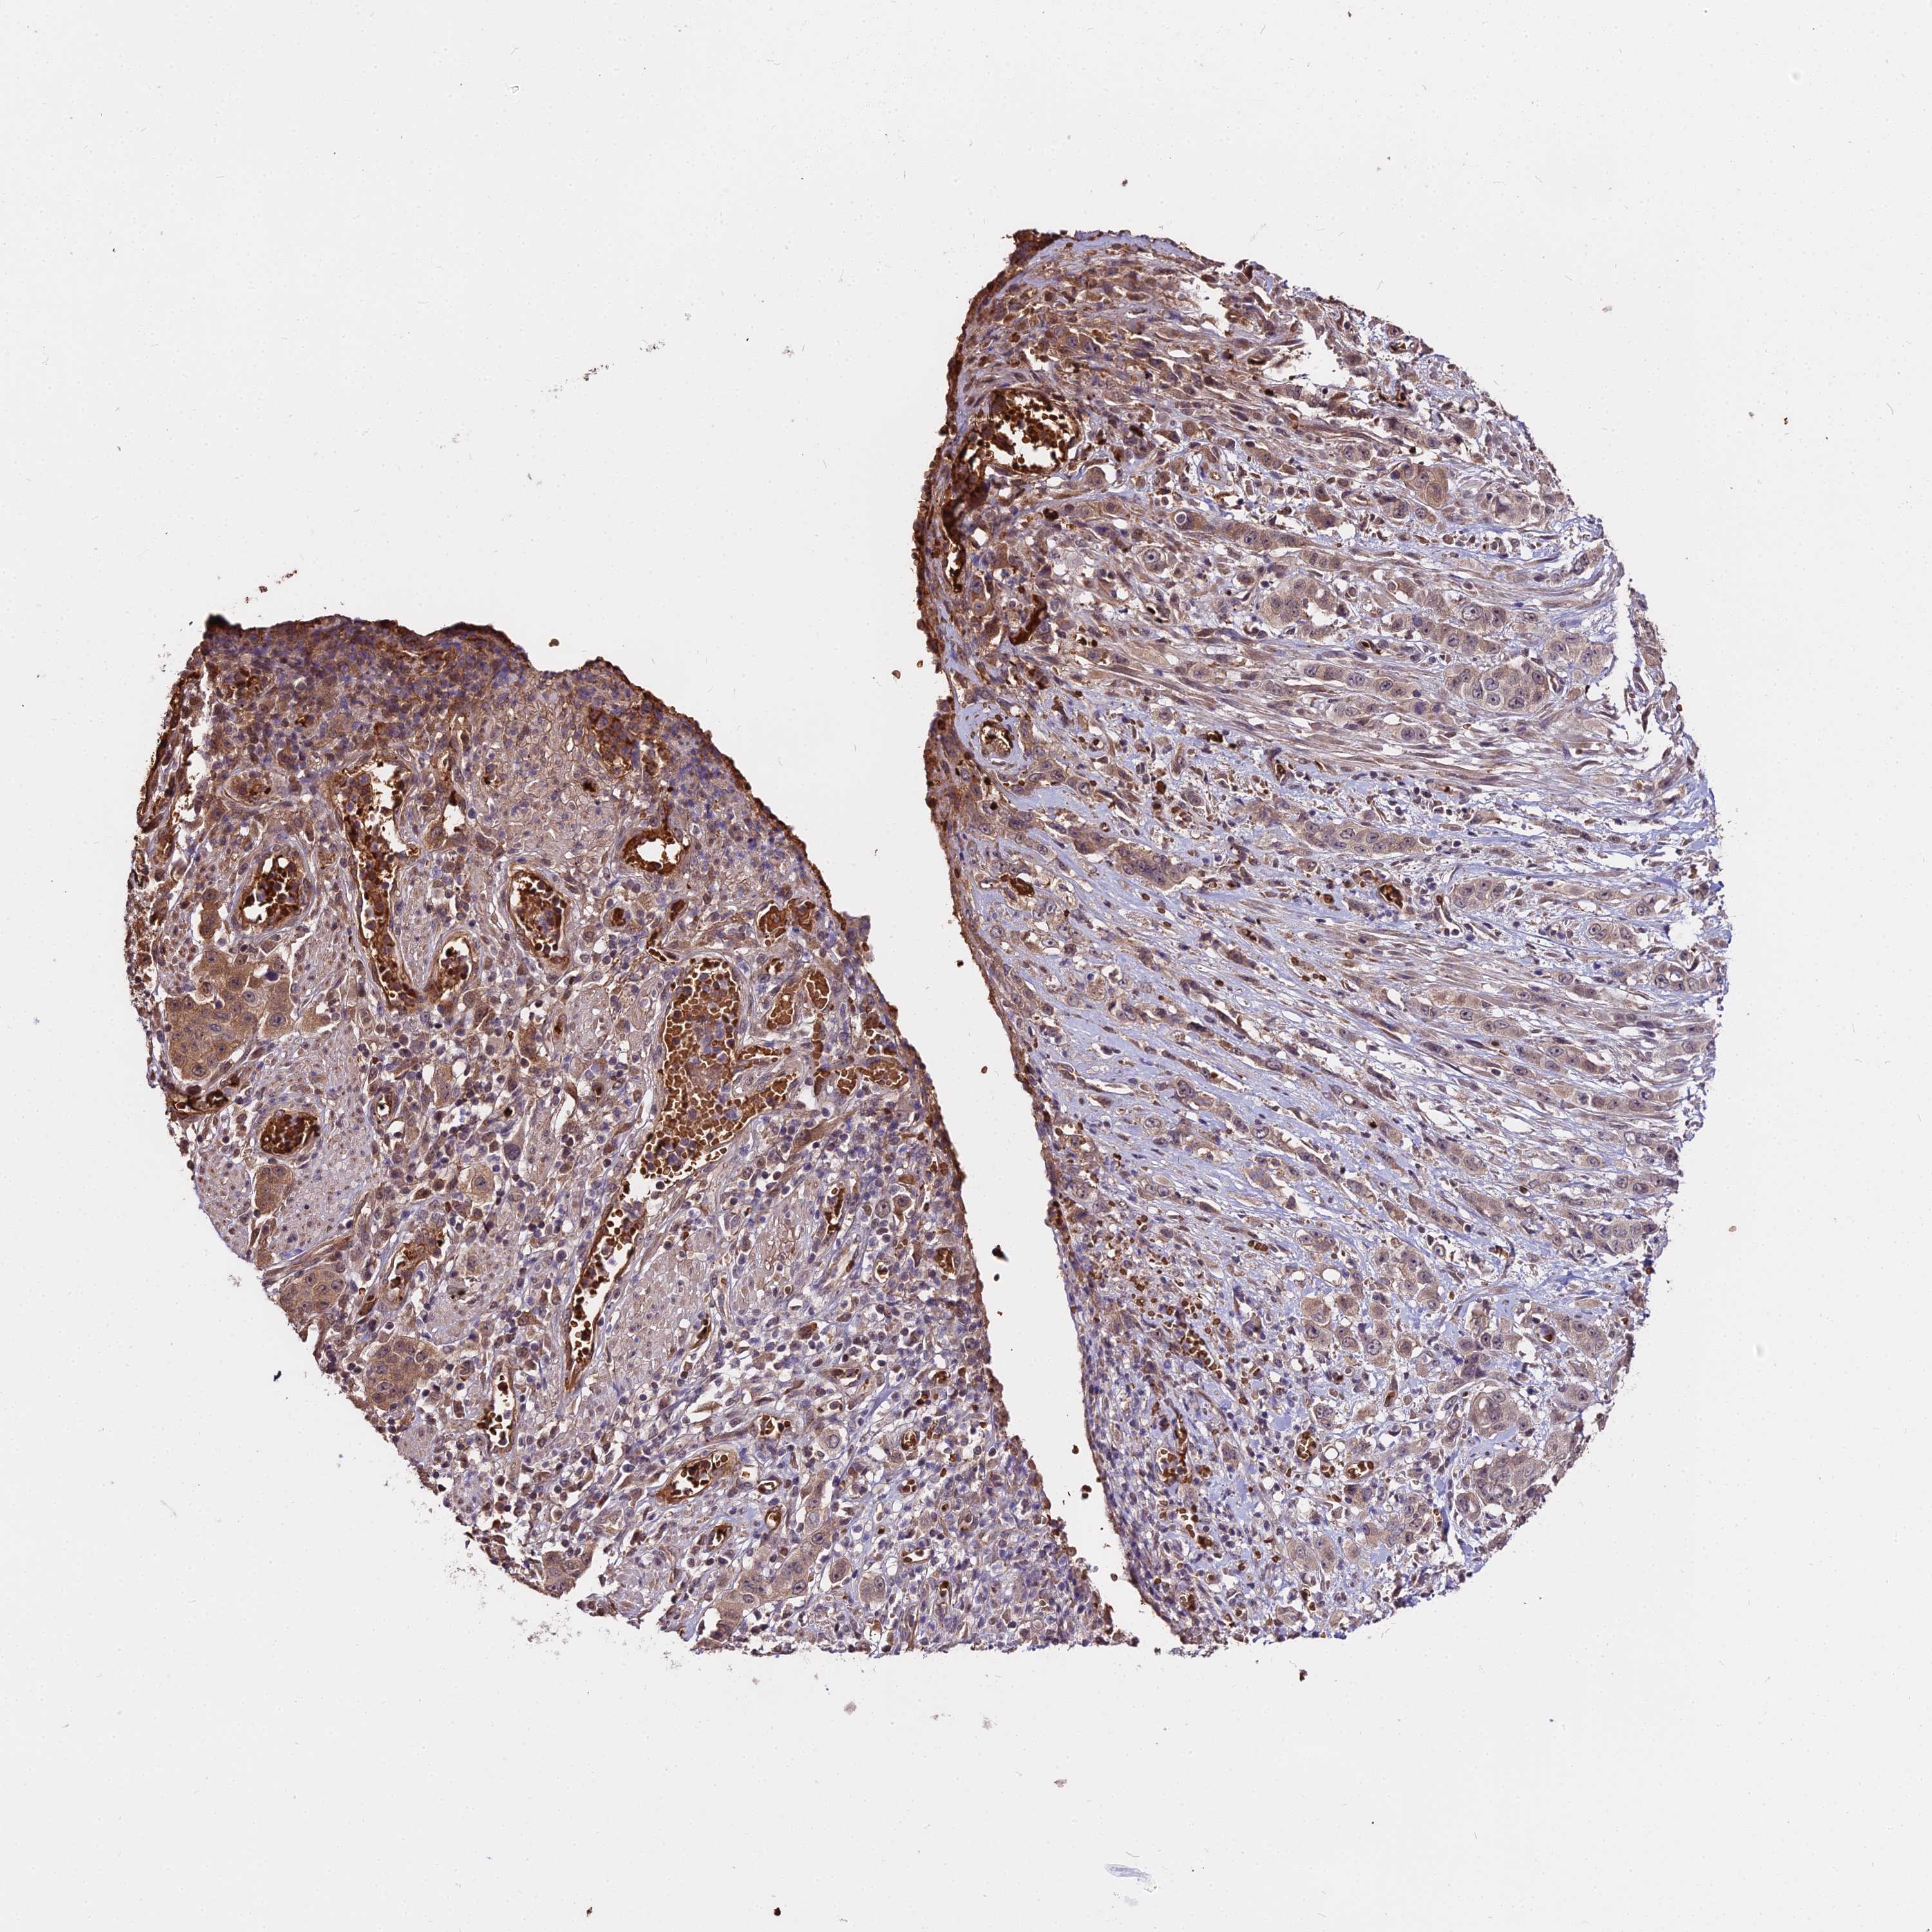

STOMACH CANCER - Protein expressioni

A mouse-over function shows sample information and annotation data. Click on an image to view it in a full screen mode. Samples can be filtered based on level of antibody staining by selecting one or several of the following categories: high, medium, low and not detected. The assay and annotation is described here.

Note that samples used for immunohistochemistry by the Human Protein Atlas do not correspond to samples in the TCGA dataset.

Antibody stainingi

Antibody staining in the annotated cell types in the current human tissue is reported as not detected, low, medium, or high, based on conventional immunohistochemistry profiling in selected tissues. This score is based on the combination of the staining intensity and fraction of stained cells.

Each image is clickable and will lead to virtual microscopy that enables deeper exploration of all samples and also displays staining intensity scores, fraction scores and subcellular localization as well as patient and tissue information for each sample.

Antibody HPA039121

Staining

High

Medium

Low

Not detected

Intensity

Strong

Moderate

Weak

Negative

Quantity

>75%

75%-25%

<25%

None

Location

Nuclear

Cytoplasmic/membranous

Cytoplasmic/membranous,nuclear

Adenocarcinoma, NOS